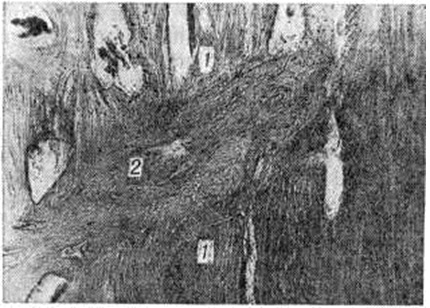

При точном сопоставлении отломков возможно прямое костное сращение с помощью интермедиарной костной мозоли, что именуют первичным костным сращением. Когда сращение отломков наступает после предварительного соединения их костно-хрящевой провизорной мозолью, на основе которой постепенно будет формироваться окончательная интермедиарная костная мозоль, говорят о вторичном костном сращении. Первичное костное сращение может произойти только в строго определённых условиях: при достаточном кровоснабжении отломков, точности их сопоставления, достаточности их обездвижения. Микрофотографии кости при первичном сращении в разные сроки консолидации представлены на рисунок 1 и 2.

В подавляющем большинстве случаев из-за трудностей обеспечения всех необходимых условий костное сращение бывает вторичным, при котором в разные сроки (но не ранее 6—8-й недель и до многих месяцев) после Переломы формируется окончательная костная мозоль. Такой вариант является проявлением адаптационных механизмов организма, направленных на восстановление целости кости в неблагоприятных условиях для заживления костных ран. Невозможность мобилизации таких приспособительных реакций приводит к несращению отломков повреждённой кости. Наиболее благоприятными для проявления адаптационных возможностей организма являются Переломы тех отделов костей, где имеется надкостница и окружающий её мышечный массив, например, диафизарные Переломы трубчатых костей. Переломы лишённых надкостницы эпифизов костей при отсутствии условий, необходимых для первичного костного сращения, не могут срастаться путём приспособительного вторичного костного сращения, поэтому без применения остеосинтеза отломки часто не срастаются, например, при медиальных Переломы шейки бедренной кости. Микрофотография кости при вторичном сращении представлена на рисунок 3.